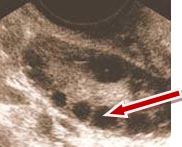

Yukarıdaki ultrason resmi bir polikistik over (yumurtalık) görüntüsüdür.

Yumurtalığın ortasında bulunan beyaz alanın çevresine dizilmiş kırmızı renkli ok ile işaret edilen siyah renkli, yuvarlak, küçük keseciklerin içinde yumurtalar bulunmaktadır.

Polikistik over sendromu olan kişilerin bir kısmında bu küçük keseciğin içinde bulunan yumurtanın gelişimi ve yumurtlama olmadığı için gebelik oluşmamaktadır.